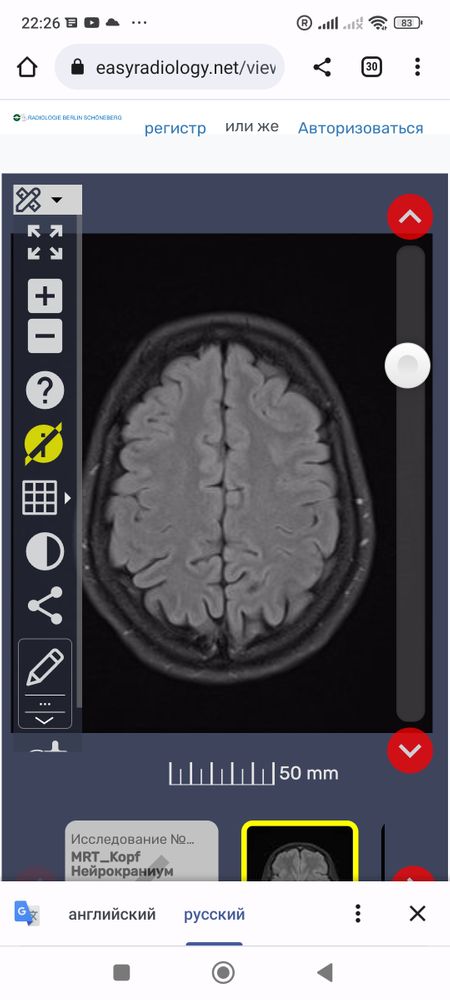

Что это за белые точки вокруг мозга? И все ли впорядке